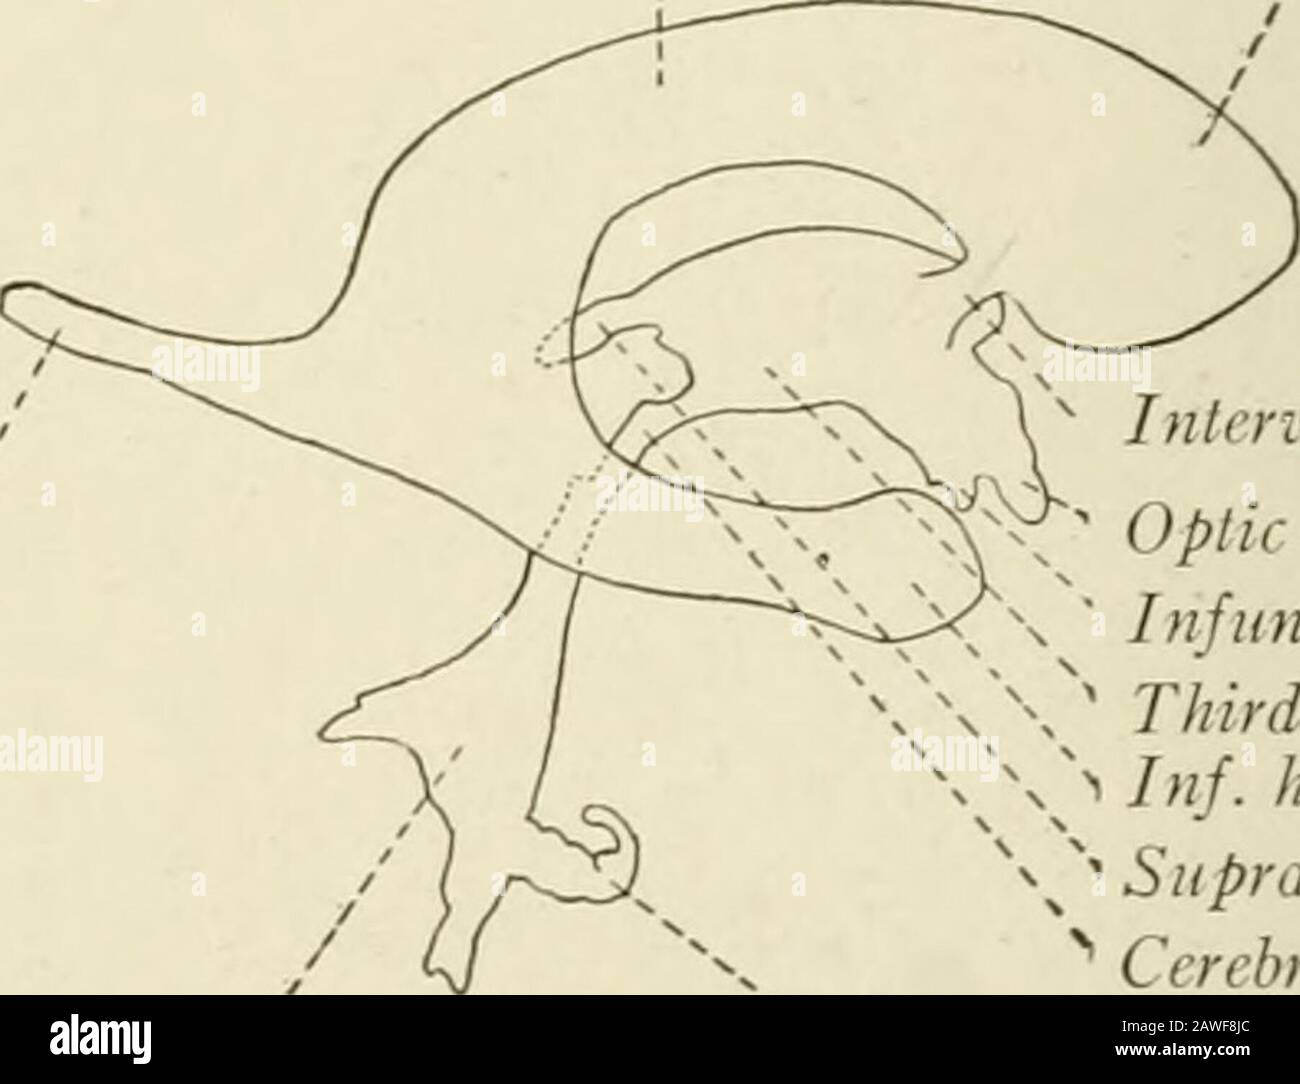

RMPFYB74–. Cunninghams Lehrbuch der Anatomie. Anatomie. PAETS abgeleitet aus dem ZWISCHENHIRN. 617 davon, welche das Aquädukt umgibt, ist direkt kontinuierlich mit der grauen Substanz der substantia perforata posterior und Tuber cinereum, und auf diese Weise kommt es zu der Oberfläche in der Unterseite des Gehirns. Die optic Chiasma kreuzen den Boden vor und markiert die Stelle, wo der Letzteren stetig mit der anterioren Wand des Hohlraums wird. Die vordere Wand des dritten Ventrikels wird durch die Lamina terruinalis, die sich nach oben erstreckt sich von der Optic chiasma gebildet. Die anteriore com-missure, wie es kreuzt von einem

RM2AWF8JC–Die Anatomie des Nervensystems, vom Standpunkt der Entwicklung und Funktion. -Ant. HornCentra, Teil Latcral vnnInf. Horn Q virale Pari Ant. Horn. Ventrikel Ventrikel Ventrikel Ventrikel Ventrikel Ventrikel Ventrikel Ventrikel Ventrikel Ventrikel Ventrikel Ventrikel Ventrikel Ventrikel Ventrikel Ventrikel Ventrikel Ventrikel Ventrikel Ventrikel ^^ 176.-Zwei Ansichten der Hirnventrikel des Menschen: A, Dorsale Ansicht; B, laterale Ansicht. Das Vorderhorn oder Cornu anterius ist der Teil, der rostral zum interventrikulären Foramen liegt. Seine Dach- und Rostrallgrenze wird von Thecorpus callosum gebildet. Sein mediales

RM2AWFNN9–Menschliche Anatomie, einschließlich Struktur und Entwicklung und praktische Überlegungen d in einem sagittalen mesialen Abschnitt (Abb. 910) wird jede dieser Teilungen als mit einem Teil des Systems der Kommunikation von Räumen verwandt angesehen, die als die dritten Ventrikel des Lateralands, der Aquädukt von Sylvius und der vierte Ventrikel die oben genannten Gehirnhemisphären ausdehnen. Durch den Hirnstamm und unter dem Kleinhirn bis zum zentralen Kanal des Rückenmarks. Da die lateralen Ventrikel zwei innumerieren, ist die Theirstellung im Zusammenhang mit den Gehirnhemisphären, in denen sie liegen, lateral zum m

RM2ANFGX0–Quain der Elemente der Anatomie. ring Abb. 729.-op ein Bild. 729. Längsschnitt durch das Gehirn OFA KÜKEN VON ZEHN DATS. (Nach Mihalkovics.) h, zerebralen Hemisphäre; olf, oKactory lobe und Nerv; St, Corpus striatum; iv, lateralventricle; ac, anterior com-missure; Er, der Lamina terminalis; ope, Optic commissure; Grube, der Hypophyse; inf inf Undi-bulum; Cai, interne carotidartery; v^, dritten Ventrikel; ch?, Choroid plexus dritter Ventrikel; Pin, zirbeldrüse; Ijg, Korpora bigemina; amv, anterior medullary Velum; unten - n - hich zwei letzte Referenzen sind das Aquädukt von Sylvius und crur

RM2CDFE0C–. Elemente der physiologischen Psychologie; eine Abhandlung über die Aktivitäten und die Natur des Geistes, aus der physischen und experimentellen Gesichtspunkten. ide,die corpora quadrigemina. Die Kavität des Neuralrohres bleibt hier klein und bildet das Aquädukt, das den Viertmit dem dritten Ventrikel verbindet. Im Zwischenhirn dehnt sich das Aquädukt in den dritten Ventrikel aus; und hier wird wieder die dorsale Wand des Tubus zu einer breiten, dünnen Membran, die in den Ventrikel gefaltet und Blutgefäße mit sich trägt. Während die zerebralen Hemisphären ihr enormes Wachstum durchlaufen, dehnt sich die Kavität mit ihnen aus, andrema